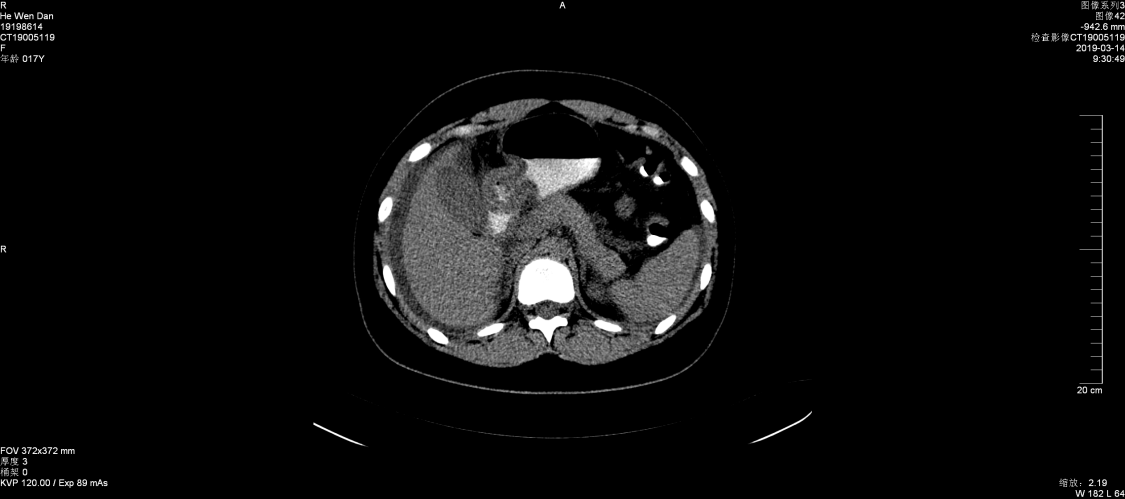

2019年3月11日,消化内科收治一名女性患者,16岁,以“腹胀1周、腹泻、腹痛1天”之主诉入院,查体:生命体征平稳,皮肤未见皮疹,心肺未见异常,腹部有柔韧感,无明显压痛,移动性浊音阳性。B超提示盆腔、腹腔积液,门诊按“急性胃肠炎”收治。入院后检查结果,血常规:白细胞22.52×109/L,嗜酸细胞比率21.2%,最高达48.6%。嗜酸细胞计数:10.81×109/L,B超提示腹膜增厚,伴大量腹水。胃镜检查:胃窦部粘膜充血、水肿,幽门狭窄,疑幽门梗阻,胃镜活检可见大量嗜酸细胞浸润。

张永红主任查房考虑为嗜酸粒细胞性胃肠炎,组织全科讨论,结合临床表现及检查结果,并排除引起嗜酸性粒细胞增多的疾病,最后诊断为:嗜酸粒细胞性胃肠炎。果断给予强的松30mg一次/日,三天后症状减轻,腹水减少,复查血常规、腹部B超较前好转,一周后患者腹水消失,症状消失,除嗜酸细胞值高以外,血常规正常,痊愈出院。建议病人定期门诊复查,目前激素仍在减量之中......